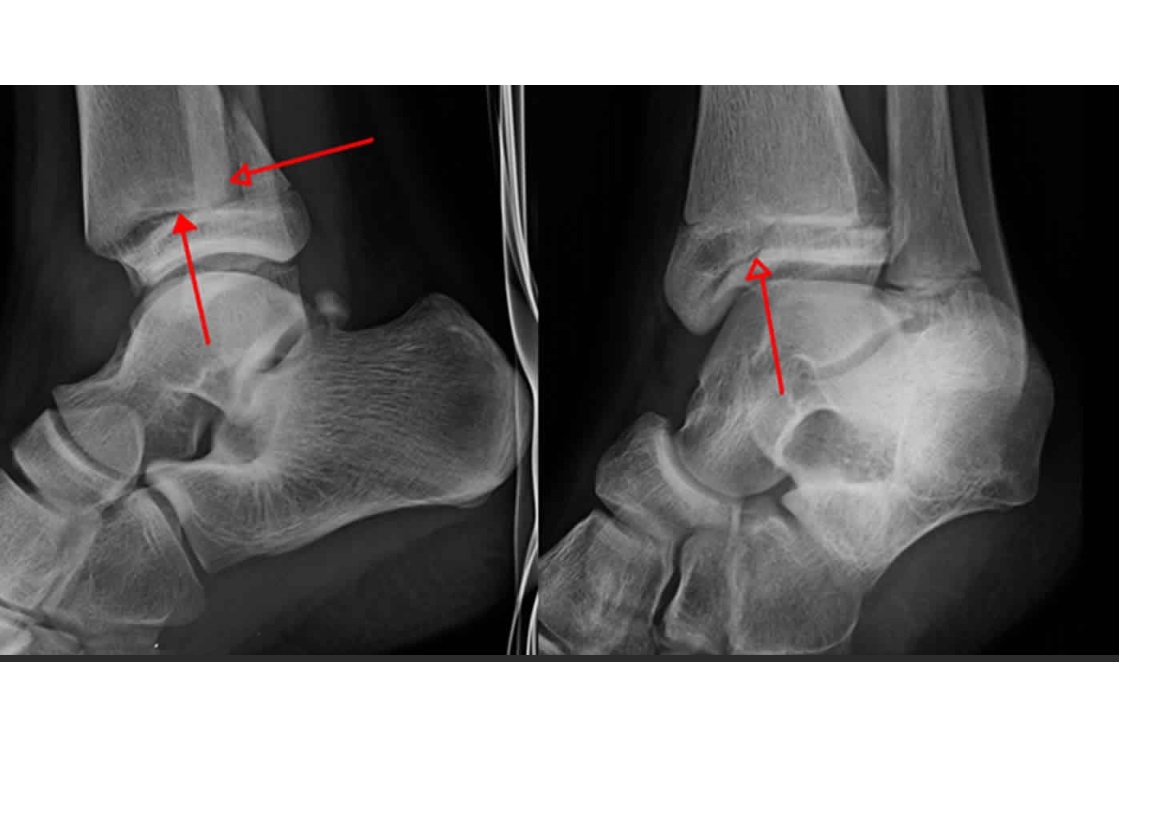

Tillaux fracture

Salter-Harris 3 = through the anterolateral distal tibial epiphysis

Triplane fracture

Salter-harris 4 =Vertical component through the epiphysis , horizontal component through the physis , oblique through metaphysis

What is bohlers line?

line drawn between the anterior and posterior borders of the calcaneus

< 20 ? fracture